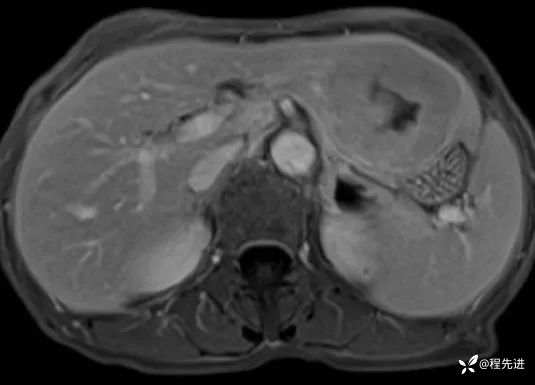

T1及T1增强4期: